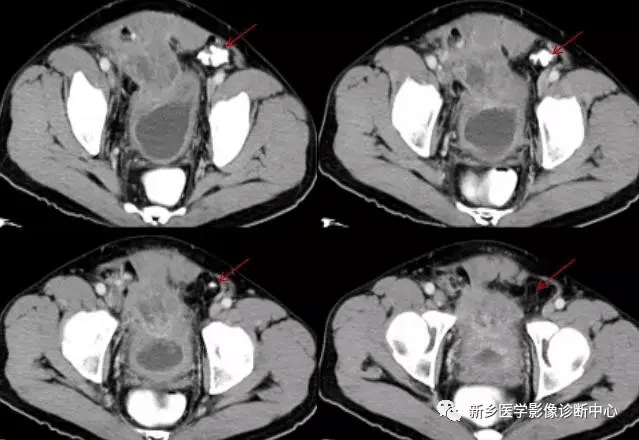

【弹簧|图解21种腹部疼痛原因】20 肾结石

文章图片